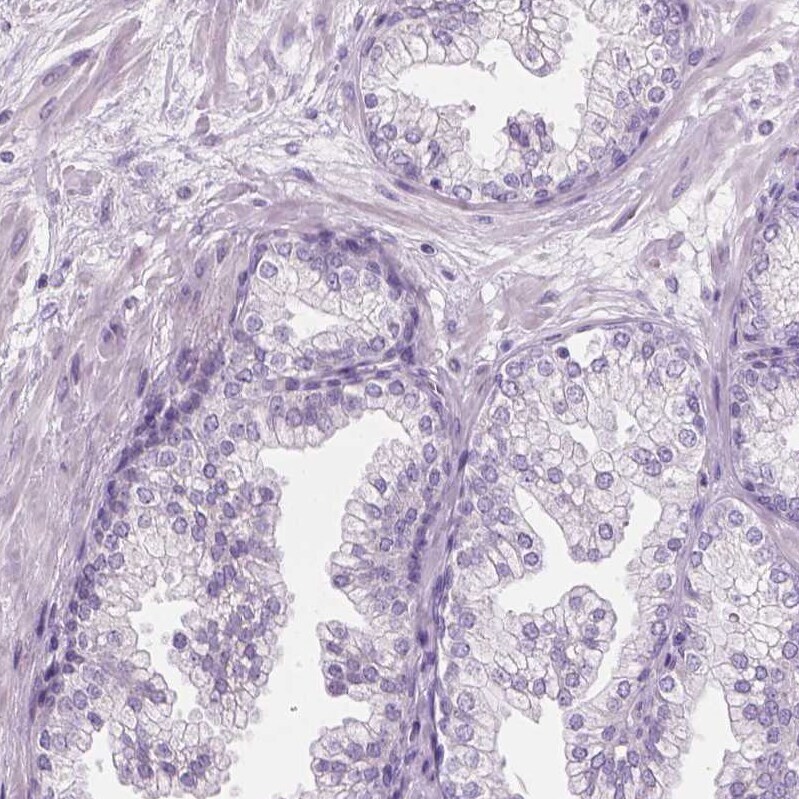

- Immunohistochemical analysis of KRT73 in human prostate using KRT73 Polyclonal Antibody (Product # PA5-83699) shows no positivity in glandular cells as expected.